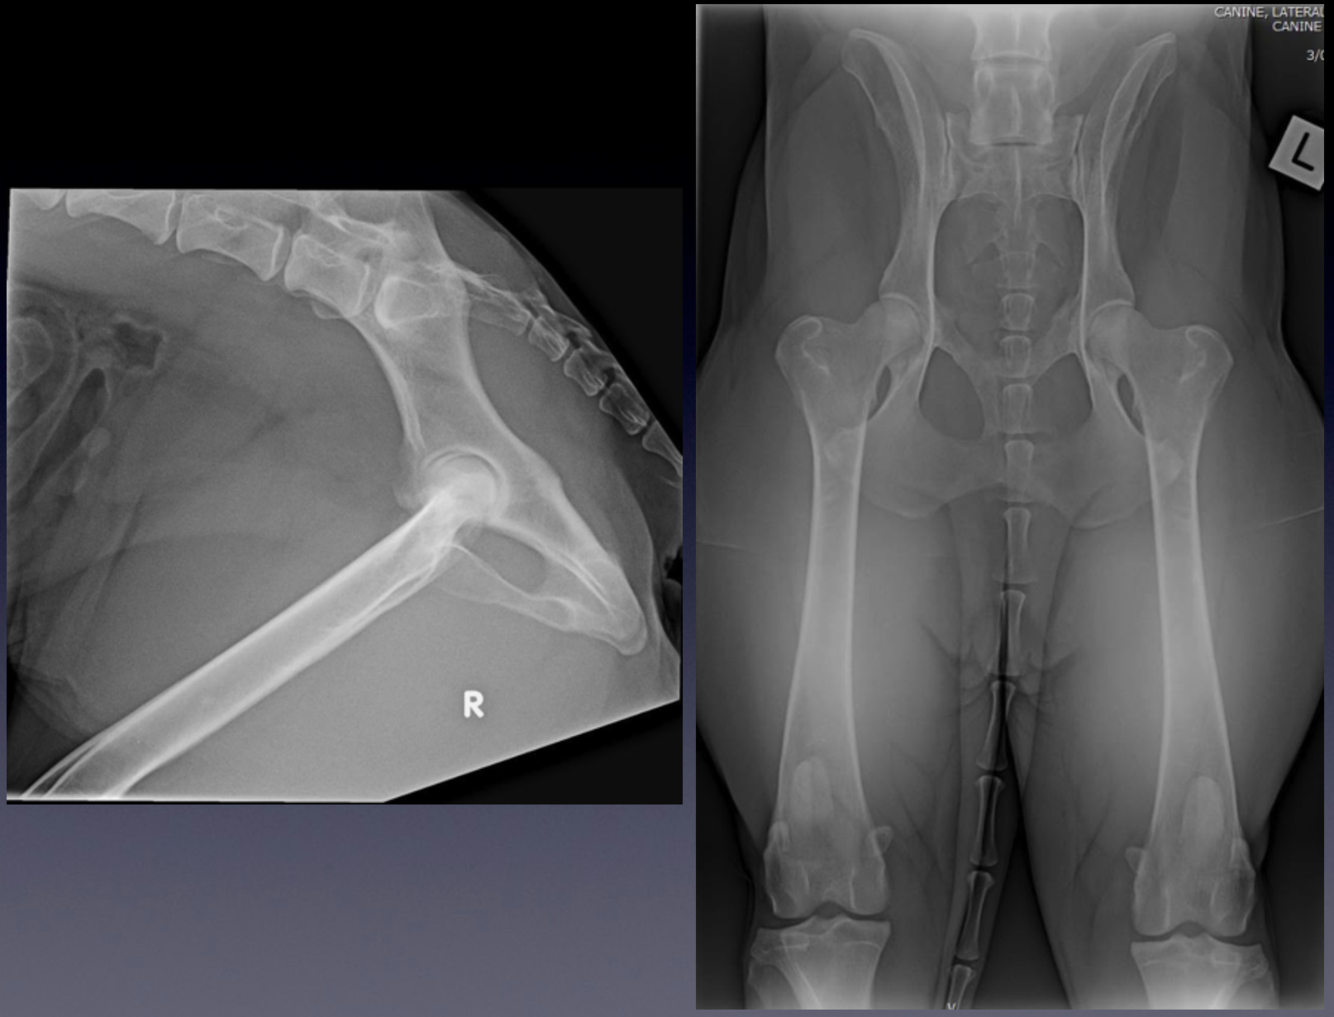

Patient number 245702 - Normal Feline Pelvis

WHAT VIEWS ARE THESE?

Use the same criteria for evaluation as in dogs.

Compare these radiographs to the canine pelvis.

•

Notice the difference in the shape of the bones between the two species, with the feline long bones

being straighter than the canine bones.

Feline vertebral bodies are longer and narrower when compared to canine vertebral bodies.

Make sure you can recognise the difference between the two species, based on the radiographic

appearance.

Did you notice the smooth solid bone ventral to and bridging L5-6 vertebral bodies? This is called ventral

vertebral spondylosis. Although this is not a normal finding, the smooth and solid nature of the bone

indicates this is an inactive process, and may be an incidental finding without any clinical significance.

Lateral and ventrodorsal (VD) hip extended projection.